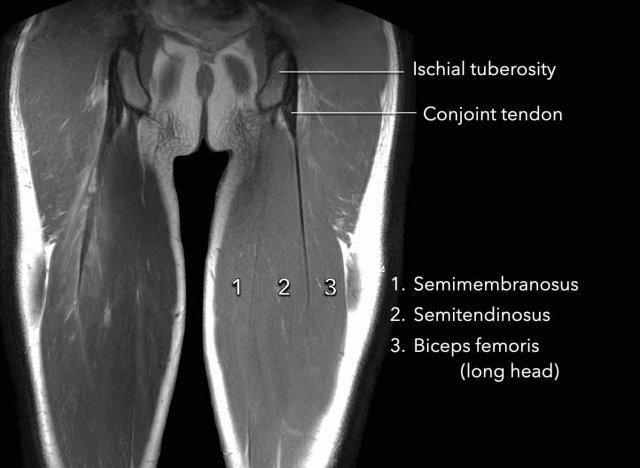

Hình ảnh giải phẫu được minh họa trên ảnh MRI mặt phẳng coronal.

Điểm bám của cơ bán gân (2) vào nguyên ủy gân kheo có một phần là mô cơ.

Gân tự do bám vào ụ ngồi và không có sợi cơ nào bám vào nó.

Ranh giới giữa gân và các sợi cơ được gọi là chỗ nối cơ-gân (musculotendinous junction).

Phần gân có các sợi cơ bám vào được gọi là gân trong cơ (intramuscular tendon).

Bản thân cơ được bao bọc bởi mạc cơ (fascia).